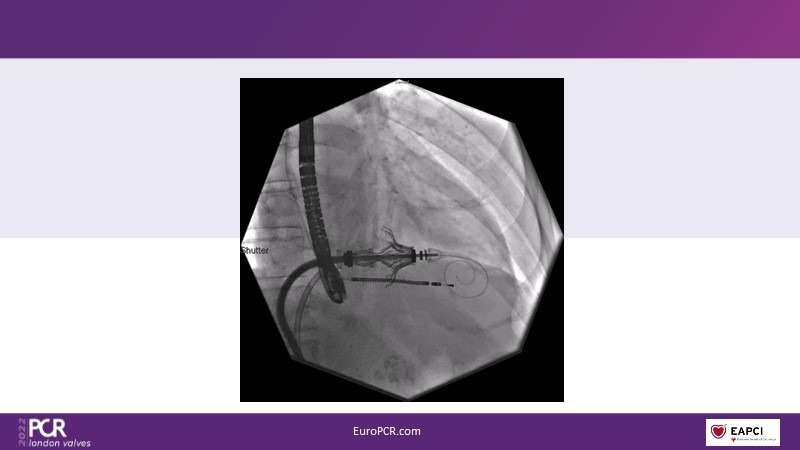

The right valves for the right ventricle: Venus MedTech tricuspid and pulmonary replacement systems

In this session from PCR London Valves 2022, discover the new Venus MedTech technology for tricuspid and pulmonary valve replacement, and a review of the clinical indications, selection criteria and procedural details.

- To learn about Venus MedTech technology, clinical indications and procedural details of valve replacement systems